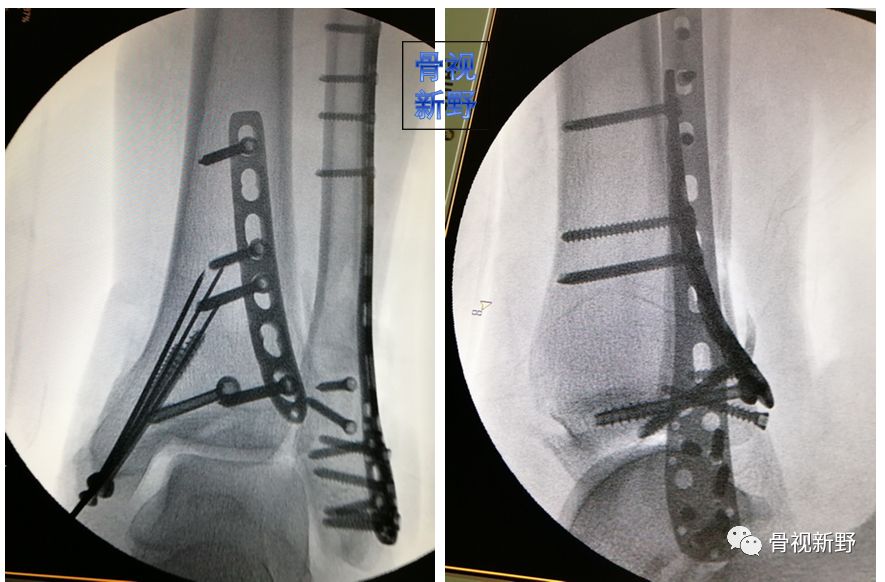

后踝/后Pilon骨折的buttress固定

后踝骨折和后Pilon骨折的界限一直不是很清楚。一般认为旋转性损伤机制、骨折块小、没有压缩的胫骨远端后方骨折属于后踝骨折,而跖屈损伤机制、骨块大、有压缩者往往属于后Pilon骨折。不稳定、较大骨块的后踝骨折及后Pilon骨折用空心钉固定有可能不能很好地中和向上的剪力,可选择butress钢板作防滑固定,以对抗垂直剪力。

锁定重建板作buttress钢板

锁定“T”型钢板作buttress钢板

3.5mm干骺端锁定钢板作buttress钢板